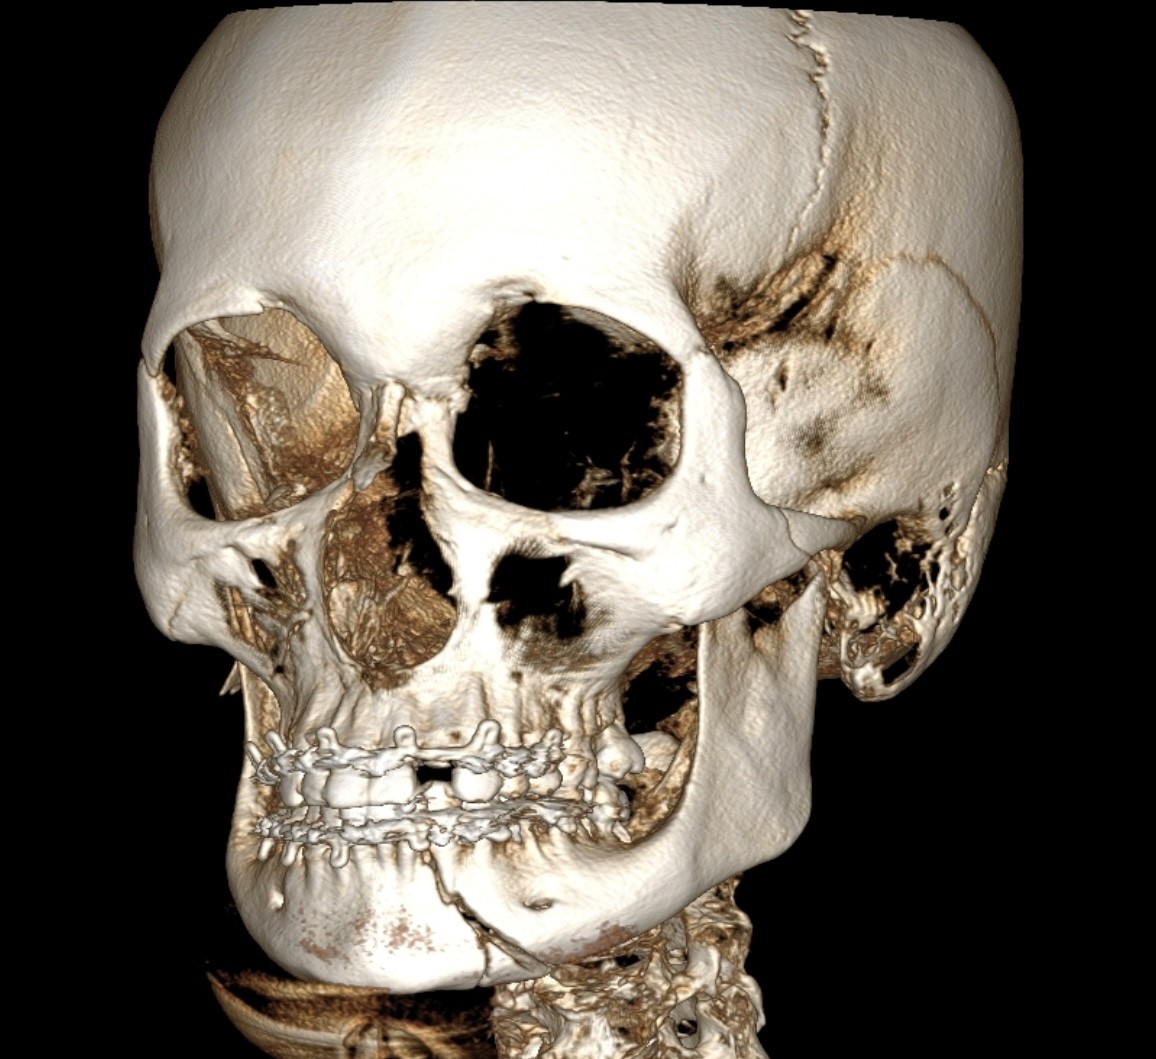

Роль КПКТ у діагностиці травм

Затримки консолідації, формування хибного суглоба, ураження зубів у зоні перелому

Лінії розлому, зміщення, фрагментацію; етапи зрощення та нормальної консолідації